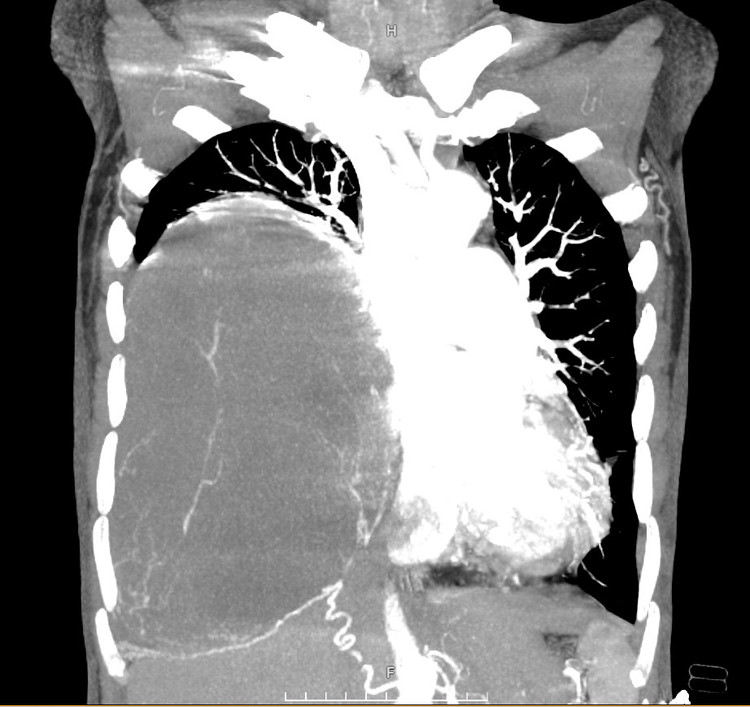

Ca mổ được thực hiện thành công, khối u lấy ra có trọng lượng hơn 2 kg. Trong mổ, bệnh nhân không phải truyền thêm máu dự trù, hồi phục tốt, được rút dẫn lưu màng phổi ngày thứ 3 sau phẫu thuật, ra viện sau 5 ngày. Giải phẫu bệnh sau mổ: u xơ màng phổi đơn độc độ mô học 1.

| Hình ảnh khối u sau khi được phẫu thuật - Ảnh BVCC |